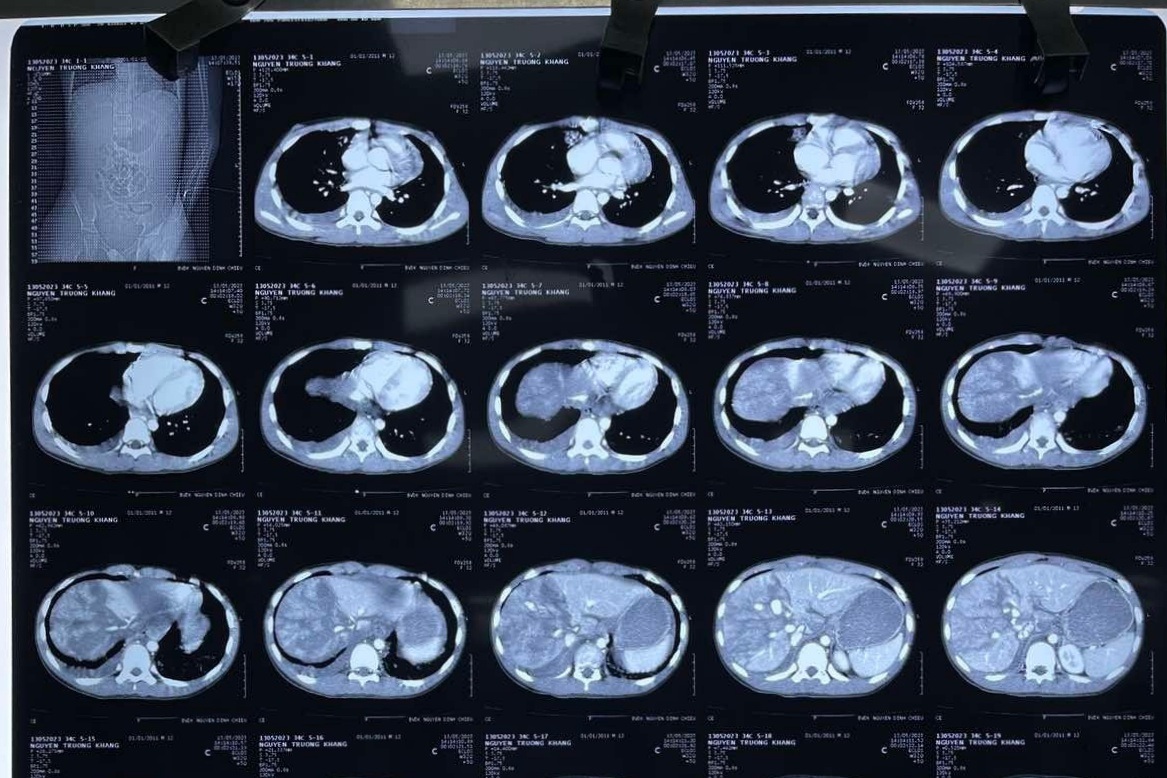

Thời điểm vào Bệnh Viện Nhi đồng Thành phố, bệnh nhi phải bóp bóng hỗ trợ thở, nằm yên, môi tái nhạt, huyết áp tụt thấp không đo được, bụng trướng căng. Qua thăm khám, các bác sĩ chẩn đoán cháu bé sốc mất máu, đa chấn thương do tai nạn giao thông, chấn thương gan độ 5 và dập phổi 2 bên.

Quá trình phẫu thuật rất căng thẳng, khi ekip điều trị phát hiện gan có vết rách phức tạp dài hơn 10cm, sâu 4cm, máu tràn đầy ổ bụng, hút được hơn 2.000ml. Toàn bộ ruột bệnh nhi bị tái, phù nề do thiếu máu nuôi.

Trước tình trạng trên, ekip gây mê phải bồi hoàn liên tục gần 4 lít máu và chế phẩm máu để giữ huyết áp sinh tồn cho bé. Cuộc mổ cấp cứu kéo dài hơn 4 giờ đồng hồ.